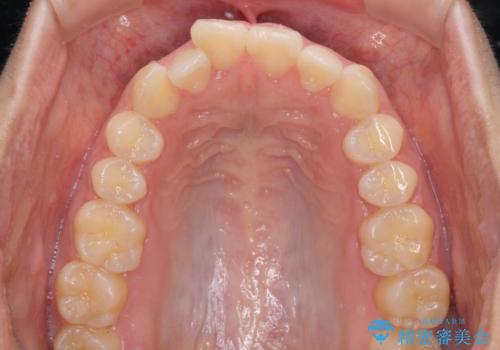

- 口が閉じにくさを気にして来院された患者様です。

上下の前歯が前方に突出していたため、上下左右の第一小臼歯4本を抜歯し、ワイヤー装置にて抜歯矯正を行うこととしました。

上下前歯部の被蓋関係を改善するの時間がかかり、3年間を要することとなりましたが、スッキリとした口元に仕上がりました。